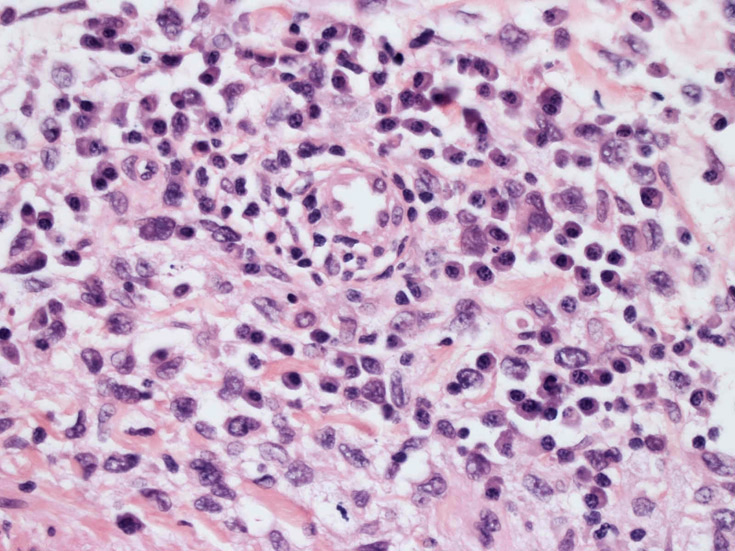

大型細胞の増殖よりなる腫瘍。縦溝,しわ,切れ込みのある核をもった大型細胞も出現する。クロマチンは顆粒状で核小体も明瞭である。核分裂は >50/10hpfと多い。eosinophilsは少ない。壊死が多発することがある。未分化ないし低分化な細胞像, 組織所見のため鑑別診断は多岐にわたり、的確な免疫染色を行う必要がある。

皮膚に異型細胞の浸潤がみられる。異型細胞は表皮内に浸潤するほか、表皮真皮境界部, 真皮, 皮下脂肪組織にもびまん, 結節様の浸潤所見を示す。血管周囲に浸潤、集蔟する所見も多く見られる。 増殖浸潤細胞の核には類円形や腎臓形, またはへこみ, 切れ込み, 溝などを有する多型な核が認められる。クロマチンは粗でvesicularな核が多い。核小体の明らかな核もある。好エオジン性の核内封入体様構造も少数に見られた。mitosisは容易に認められる。hyperchromaticな多型核, bizzarreな細胞が高頻度に認められ異型度は高いと考えられる。細胞質は境界不明瞭, 淡明または泡沫様の 好エオジン性胞体である。